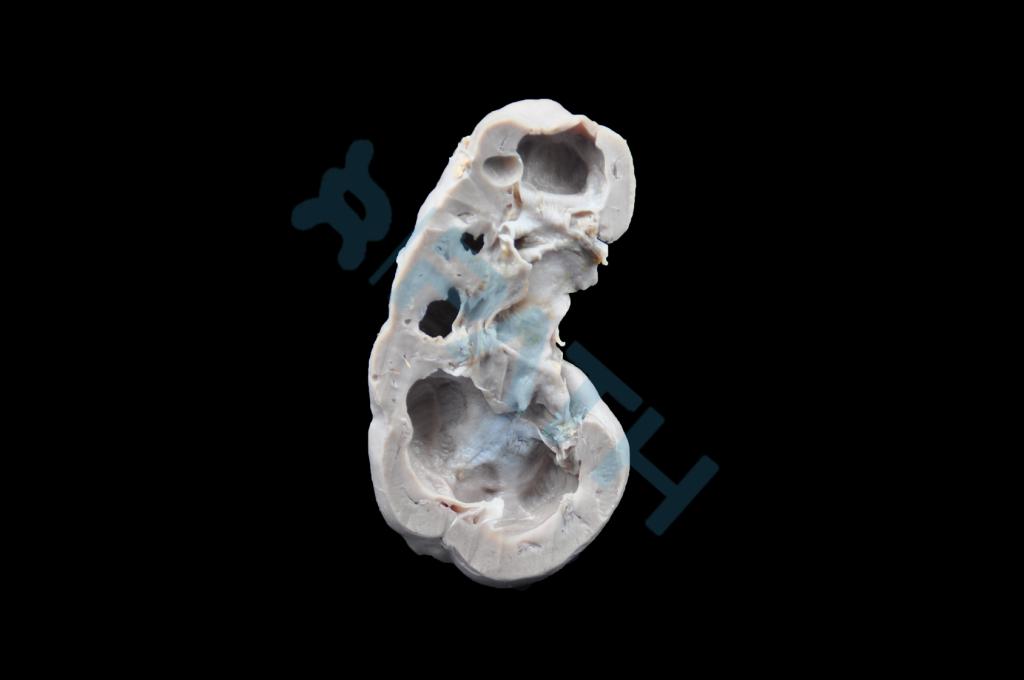

肾脏压迫性萎缩

肾水肿